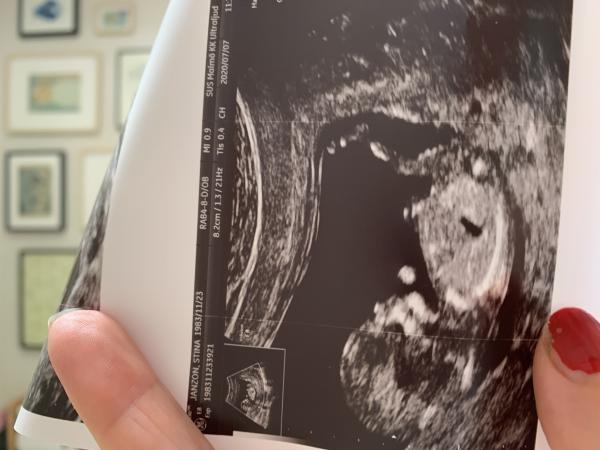

Var på kub idag och enligt nub-teorin kan man se kön redan då. Men jag lyckas inte tyda bilderna. Var så lätt med mina två tidigare. Kan ni gissa?! Blir lyckligt för vad som helst????

Åh, jag tror precis tvärtom :) Jag tycker att det är en solklar flick-nub! Om du kollar vinkeln mellan nuben och ryggraden så ser du att den understiger 30 grader: